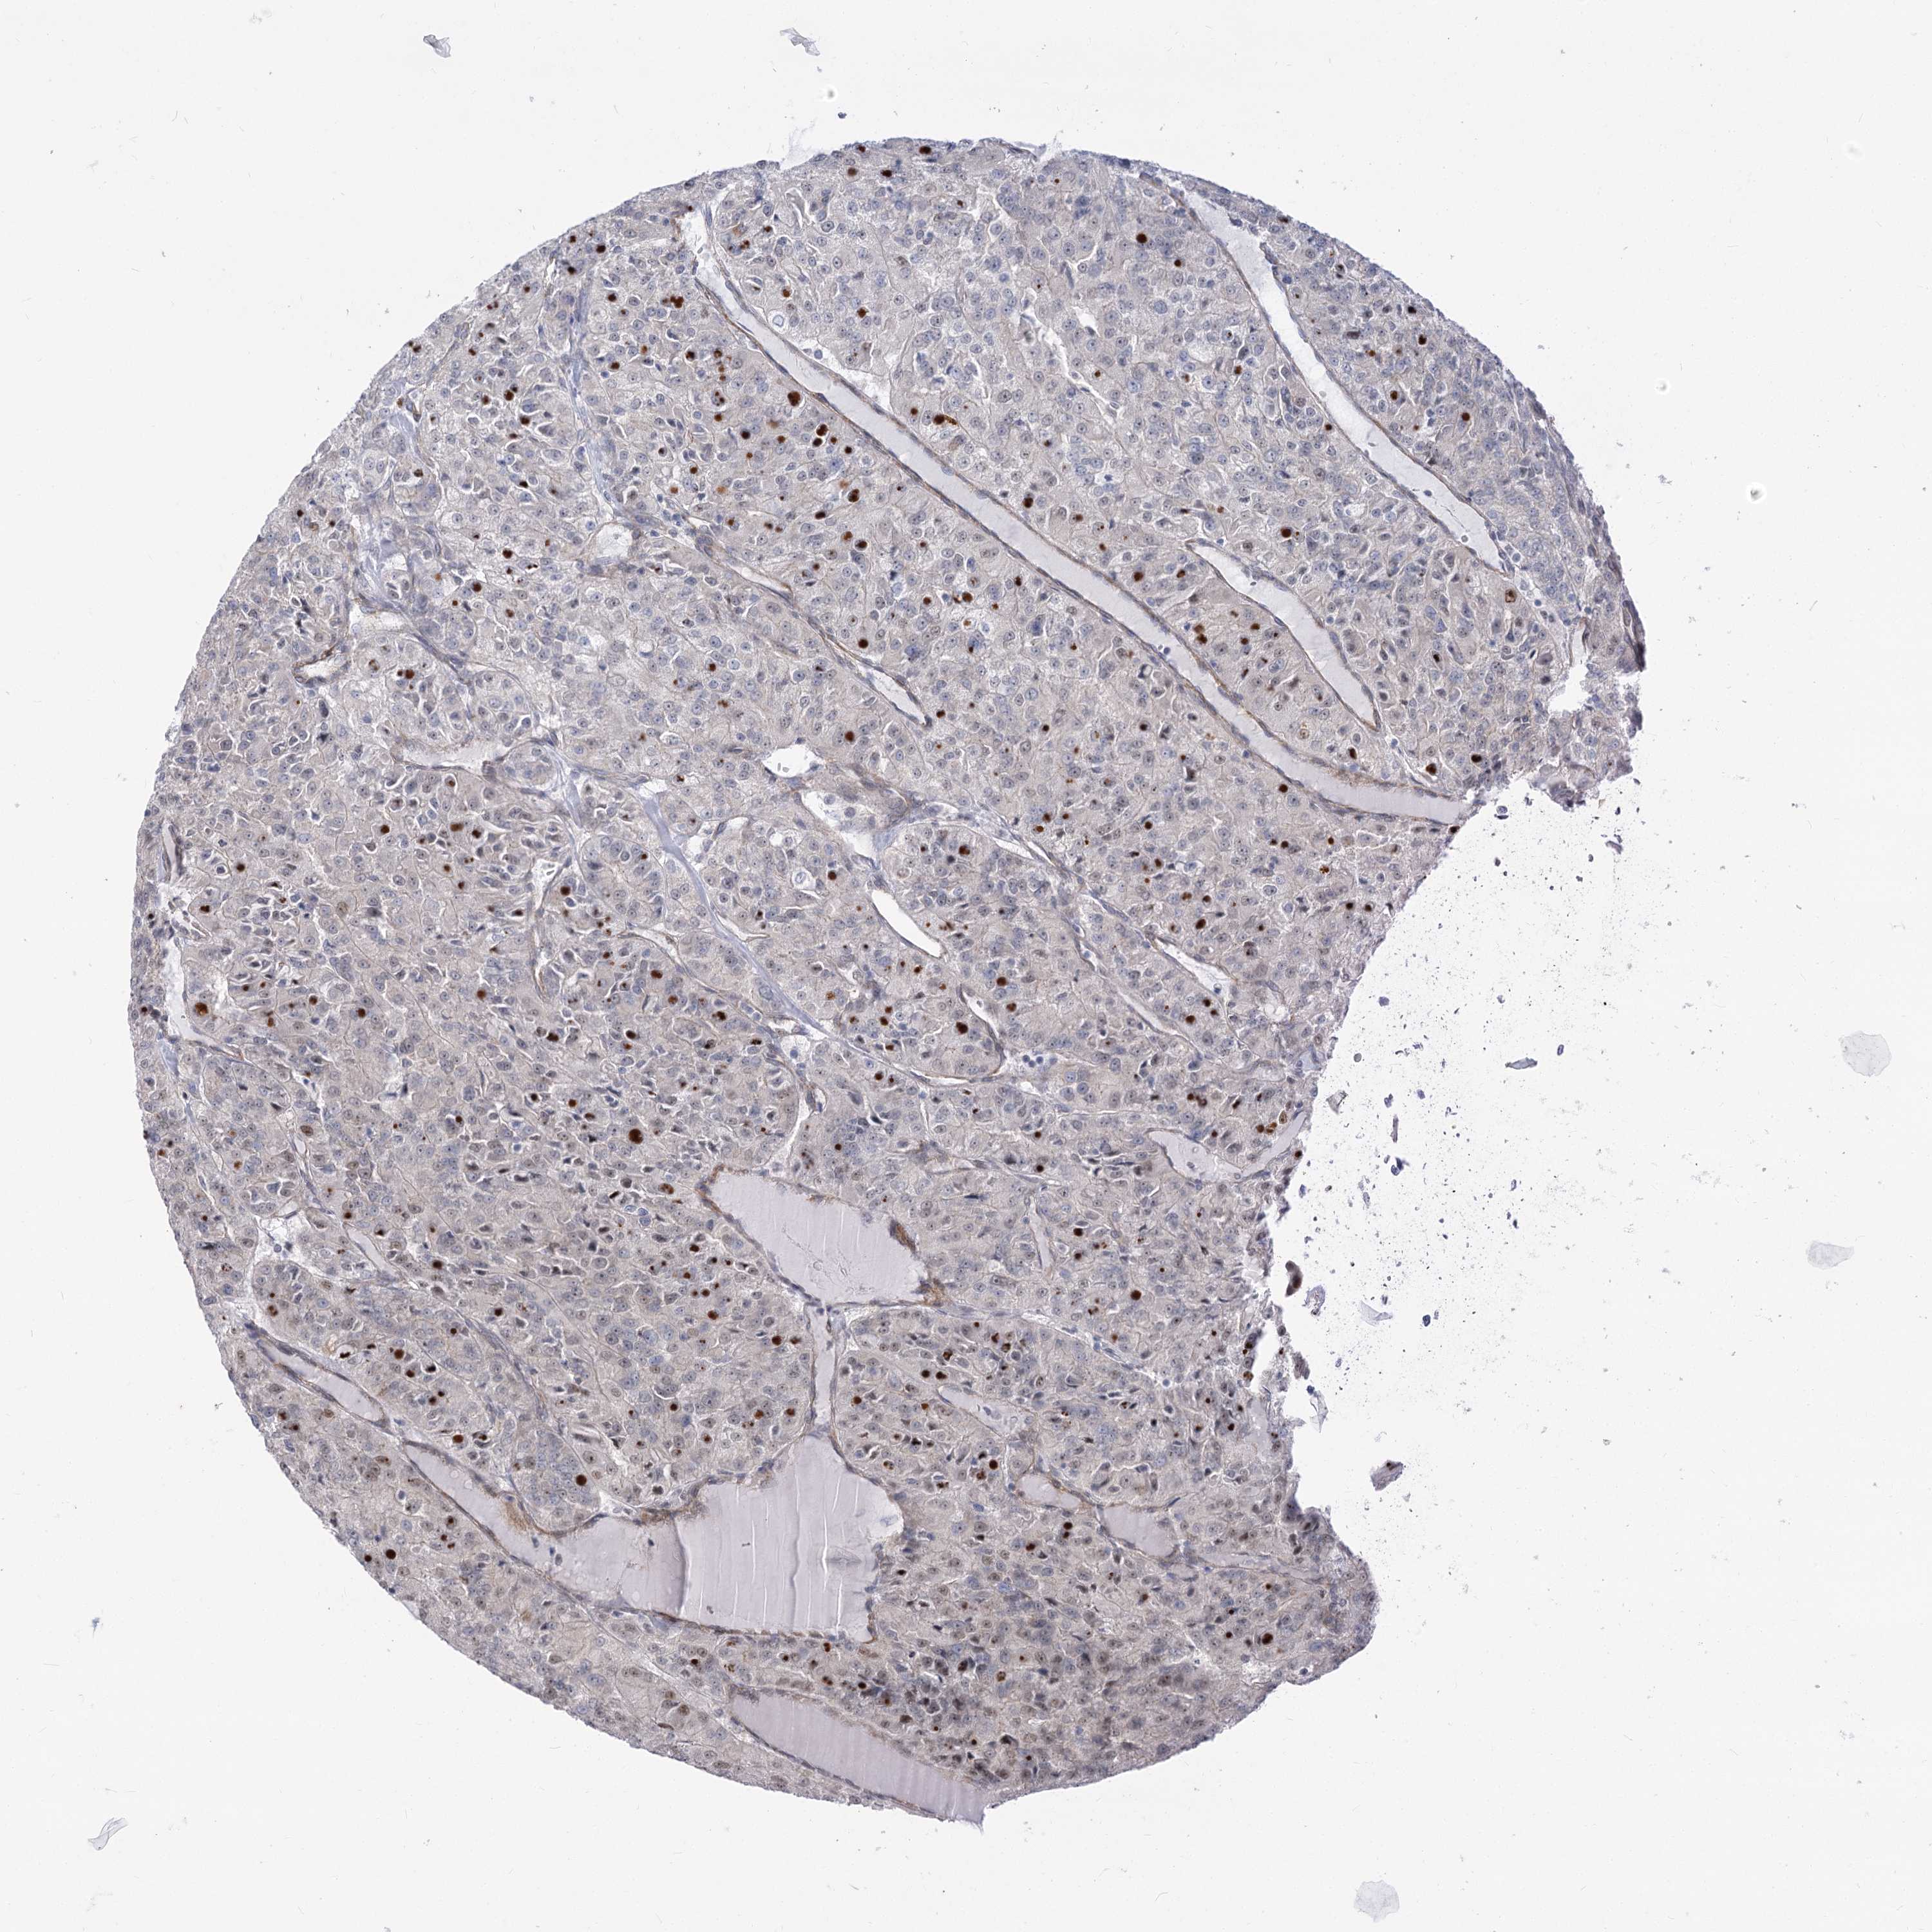

CANCER RENAL CANCER Show tissue menu

KICH TCGA KIRC TCGA KIRC VALIDATION KIRP TCGA PROTEIN RCC CPTAC PROTEIN EXPRESSION